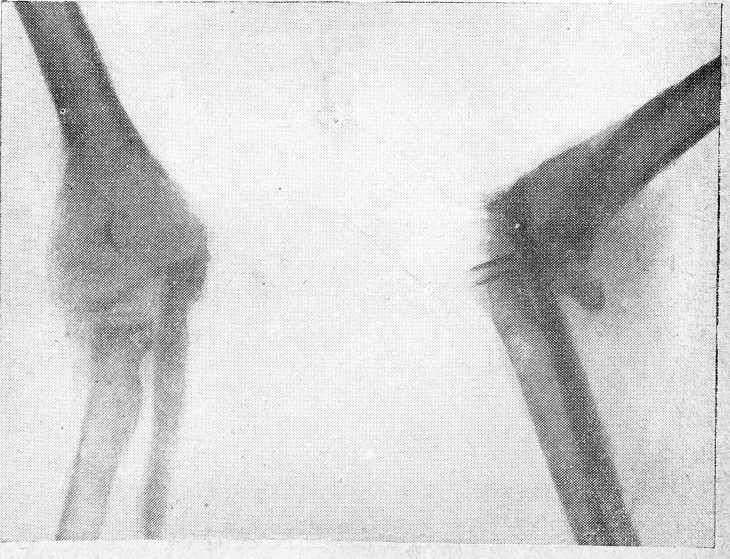

2-й случай. Н. К., 13 лет, поступил в клинику с жалобами на боли в правом локтевом суставе с ограничением движений в нем. В январе 1935 года был ушиб правого локтевого сустава; после ушиба в области сустава стала расти опухоль. 4/IV—повторный ушиб того же локтевого сустава. Имеющаяся опухоль на суставе после вторичного ушиба стала быстро расти; боли усилились, и движения в суставе стали ограничены.

Правое плечо атрофировано по сравнению с левым. В области правого локтевого сустава на предплечье, на задней поверхности имеется плотная костной консистенции опухоль с гладкой поверхностью, неподвижная, безболезненная на опухоли в области всего локтевого сустава заметны расширенные подкожные вены. Сгибание и разгибание в локтевом суставе ограничены. На рентгеновском снимке: в дистальном участке локтевой кости кистозная опухоль с ясно видимыми перемычками.

Рис. 3. 2-й случай. Николай К., 13 лет, до операции.

Реакция Касони отрицательная. 27/IV—операция под общим наркозом. Проксимальный отдел локтевой кости представляет кистозную веретенообразно раздутую опухоль; опухоль резецирована в пределах здоровой костной ткани. Дефект локтевой кости заполнен костным штифтом, взятым из правой больше-берцовой кости, 8 см длиною, 1½ см в поперечнике. Операционная рана на предплечье и голени зашита наглухо. Гипсовая повязка на всю руку. Локтевой сустав в положении сгибания под углом в 90°. На 17-й день после операции выписан в гипсовой повязке с нормальной температурой и в хорошем состоянии. Гистологический диагноз: фиброзный остит.

Через шесть месяцев у больного в области трансплантированного штифта констатирована плотная костная мозоль и полный объем движения в локтевом сочленении (рис. 3 и 4).

Рис. 4. Николай К., 13 лет, после операции.